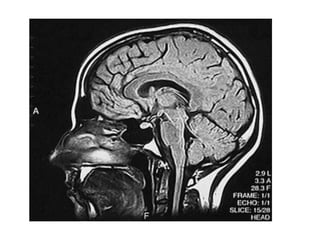

Grayscale or Greyscale Image

Value of each pixel is a single sample; it

Also known as black-and-white, are

composed exclusively of shades of gray;

varying from black at weakest intensity to

white at strongest

Grayscale images have many shades of gray